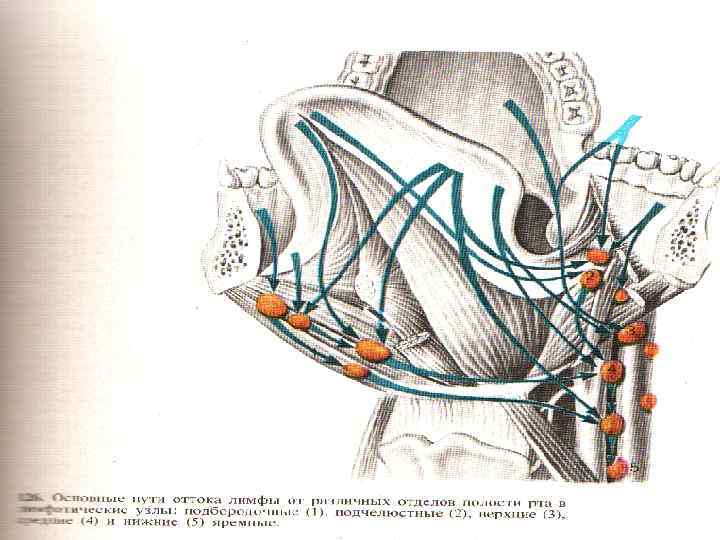

Регионарное метастазирование Регионарные лимфоузлы: поверхностные и глубокие лимфоузлы шеи. При раке средне-боковых поверхностей и кончика языка – в подчелюстные, средние и глубокие лимфоузлы шеи; Рак задней половины языка – верхние глубокие шейные лимфоузлы; Рак слизистой оболочки щеки, дна полости рта и альвеолярного края нижней челюсти – подчелюстные лимфоузлы; Рак передних отделов полости рта – подбородочные лимфоузлы; Рак задних отделов – средние и верхние яремные лимфоузлы.

Регионарное метастазирование Регионарные лимфоузлы: поверхностные и глубокие лимфоузлы шеи. При раке средне-боковых поверхностей и кончика языка – в подчелюстные, средние и глубокие лимфоузлы шеи; Рак задней половины языка – верхние глубокие шейные лимфоузлы; Рак слизистой оболочки щеки, дна полости рта и альвеолярного края нижней челюсти – подчелюстные лимфоузлы; Рак передних отделов полости рта – подбородочные лимфоузлы; Рак задних отделов – средние и верхние яремные лимфоузлы.